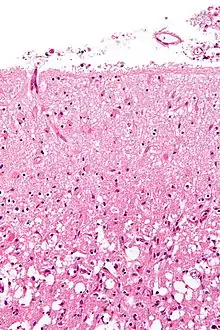

الفسيولوجيا المرضية

السكتة الدماغية الاسكيمية

تحدث السكتة الدماغية بسبب فقدان تدفق الدم إلى جزء من الدماغ، تبدأ بسلسة الإشلال الاسكيمي.[46] تتوقف انسجه الدماغ عن العمل العمل إذا حرمت من الأكسجين لأكثر من 60 إلى 90 ثانية بعد ثلاث ساعات تكون الانسجه قد ماتت أي اصابها احتشاء وتتاثر تلك المنطقة في وظيفتها ويصاب المريض باصابه لارجعه فيها (وهذا هو السبب يتم إعطاء الادويه المميته للدم مثل alteplase حتى ثلاث ساعات منذ بداية السكتة الدماغية.) تصلب الشرايين قد يعطل امدادات الدم عن طريق تضييق التجويف الأوعية الدموية مما يؤدي إلى الحد من تدفق الدم، مما يتسبب في تشكيل جلطات الدم داخل الاوعية. و يحدث [47] احتشاء صمي عندما تتشكل الصمات في أماكن أخرى في الدورة الدموية، وعادة في القلب نتيجة الرجفان الأذيني، أو في الشرايين السباتية، ومن ثم يدخل الدورة الدموية الدماغية، ويعمل على تسكير الأوعية الدموية في الدماغ. منذ يتم تسكير الأوعية الدموية في الدماغ، يصبح في الدماغ انخفاض في الطاقة، وبالتالي فإنه يلجأ إلى استخدام الأيض اللاهوائي داخل المنطقة المتاثره بنقص التروية. الأيض اللاهوائي تنتج أقل الأدينوساين ثلاثي (ATP) من الطاقة ولكنه يطلق كل إنتاج الوحدة لطاقة الحمض يسمى حمض اللبنيك. حامض اللبنيك وقد يعمل هذا الحمض على تدمير الخلايا لأنه هو من الأحماض وبالتالي فان التوازن الحمضي القاعدي في الدماغ قد يتعطل. يشار إلى منطقة نقص التروية باسم "الغبش الدماغي ".[48] يتسبب نقص الأكسجين في فشل عمليات العصبون الطبيعية المسئولة عن إنتاج ثلاثي فوسفات الأدينوسين (ATP) اللازم لإنتاج الطاقة. تنتقل الخلايا إلى الأيض اللاهوائي، وتنتج الحمض اللبني. تفشل مضخات نقل الأيونات التي تعتمد على ثلاثي فوسفات الأدينوسين، مما يتسبب في إزالة استقطاب الخلية، ويسمح للأيونات بما فيها الكالسيوم، (Ca++) بالتدفق إلى الخلية. لا تتمكن مضخات الأيونات من نقل الكالسيوم خارج الخلية بعد ذلك، وترتفع مستويات الكالسيوم داخل الخلية ارتفاعًا حادًا. يحفز وجود الكالسيوم إطلاق غلوتومات الناقل العصبي للحمض الأميني الإثاري. تعمل الغلوتومات على تحفيز مستقبلات إيه إم بي إيه (AMPA) ومستقبلات إن إم دي أيه (NMDA) المنفذة للكالسيوم (Ca++) التي تنفتح لتسمح بدخول المزيد من الكالسيوم إلى الخلية. يزيد الدخول المفرط للكالسيوم من تهيج الخلية، مما يتسبب في إنتاج الكيماويات الضارة؛ مثل الجذور الكيميائية الحرة وأنواع الأكسجين التفاعلية والإنزيمات التي تعتمد على الكالسيوم مثل الكالبين ونوكليازات الاقتطاع الداخلية والأتبازات (ATPase) والفسفوليبازات في عملية تسمى التسمم الاستثاري .[49] ويمكن للكالسيوم أيضًا أن يتسبب في إطلاق المزيد من الغلوتومات. بينما تعمل الفسفوليبازات على تحطيم الغشاء الخلوي، فإنه يصبح أكثر نفاذية، ويسمح بتدفق المزيد من الأيونات والكيماويات الضارة إلى داخل الخلية. تتحطم المتقدرة، مما يتسبب في إطلاق السموم وعوامل الاستماتة إلى داخل الخلية. يبدأ شلال الاستماتة التي تعتمد على الكاسباز، مما يتسبب في "انتحار" الخلايا. إذا ماتت الخلية بسبب النخر، فإنها تُطلق الغلوتومات والكيماويات السامة في البيئة المحيطة بها. تتسبب السموم في تسميم العصبونات المجاورة، كما تستطيع الغلوتومات أن تزيد من استثارتها. عند إعادة إرواء الدماغ، تتسبب مجموعة من العوامل في إصابة إعادة الإرواء. تزداد الاستجابة الالتهابية، وتبتلع الخلايا البلعمية الأنسجة التالفة التي لازالت قابلة للحياة. تتسبب الكيماويات الضارة في تدمير الحاجز الدموي الدماغي. تحدث الوذمة الدماغية (تورم الدماغ) بسبب تسرب الجزيئات الكبيرة، مثل الألبومينات من الأوعية الدموية عن طريق الحاجز الدموي الدماغي التالف. وتتسبب هذه الجزيئات الكبيرة في دخول المياه إلى نسيج الدماغ بعدها عن طريق التناضح. وتتسبب هذه "الوذمة وعائية المنشأ" في ضغط نسيج الدماغ وتدميره.[50] الإسكيمية تحرك أيضا إنتاج الجذور الحرة للأكسجين وغيرها من أنواع الأكسجين التفاعلي. هذه تتفاعل مع وتضر أيضا عددا من العناصر الخلوية والخارجية. الأضرار التي لحقت بطانة الأوعية الدموية أو البطانة أمر بالغ الأهمية. في الواقع ، يعمل العديد من البروتينات العصبية المضادة للأكسدة مثل حمض اليوريك و NXY-059 على مستوى البطانة وليس في المخ في حد ذاته. تبدأ الجذور الحرة أيضًا بشكل مباشر عناصر من سلسلة موت الخلايا المبرمجة عن طريق إشارات الأكسدة والاختزال.[51]

هذه العمليات هي نفسها بالنسبة لأي نوع من الأنسجة الدماغية ويشار إليها مجتمعة باسم تتالي الدماغية. ومع ذلك، فإن أنسجة المخ معرضة بشكل خاص للإسكيمية لأنها تحتوي على احتياطي تنفسي ضئيل وتعتمد بشكل كامل على الأيض الهوائي، على عكس معظم الأعضاء الأخرى. بالإضافة إلى أثرها التدميري على خلايا الدماغ، تتسبب ال ischemia and infarction بخسارة السلامة البنيوية لخلايا الدماغ والأوعية الدموية عبر تسببها بإطلاق إنزيمات مثل matrix metalloproteases والتي هي عبارة عن إنزيمات تحتوي الزنك والكالسيوم وتؤدي إلى تكسر الكولاجين، حمض الهيالورونيك، ومكونات أخرى من الأنسجة الضامة. وتسهم إنزيمات متعددة بالإضافة إلى matrix metalloproteases في هذا الأثر التدميري. أما تدمير السلامة البنيوية للأوعية الدموية فيتسبب بانهيار الحاجز الدموي-الدماغي مما يسهم في حدوث الاستسقاء الدماغي والذي يتسبب بدوره في المزيد من الإصابة الثانوية للدماغ.